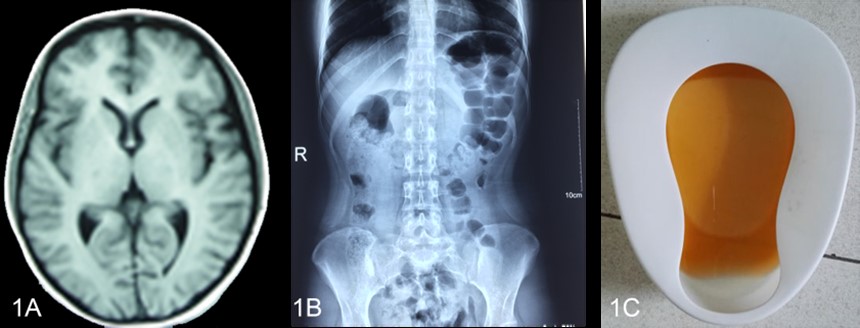

先证者2016年4月开始发病,先后多家医院诊断为“胃肠炎”、 “不完全肠梗阻”、“癫痫”,并伴有低钠血症、低钾血症、高胆红素血症、持续性的下肢无力和疼痛,窦性心动过速,高血压、贫血、肝损伤,胰酶升高。在住院期间,曾排出棕色尿液促进了对AIP的诊断。最终,尿PBG阳性和尿铅阴性确认了AIP。

A 头颅MRI显示正常 B腹部平片示肠胀气 C 棕色尿液

图1-1 先证者发作的临床资料